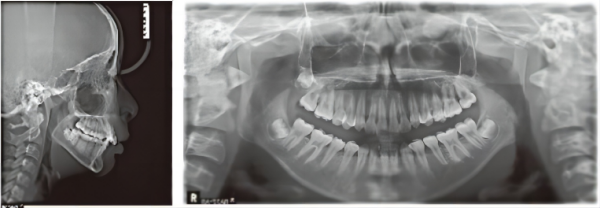

X線

矢状平面の問題: クラスIIの不正咬合、深いオーバーバイト。

垂直平面の問題: 前歯の深いオーバーバイト。

水平面の問題: 顎歯列弓は中央部で幅が広すぎますが、下顎歯列弓は狭いです。

歯科用アーチの問題: 混雑したへこみアルアーチ、左側の小臼歯の両側のはさみの咬傷。